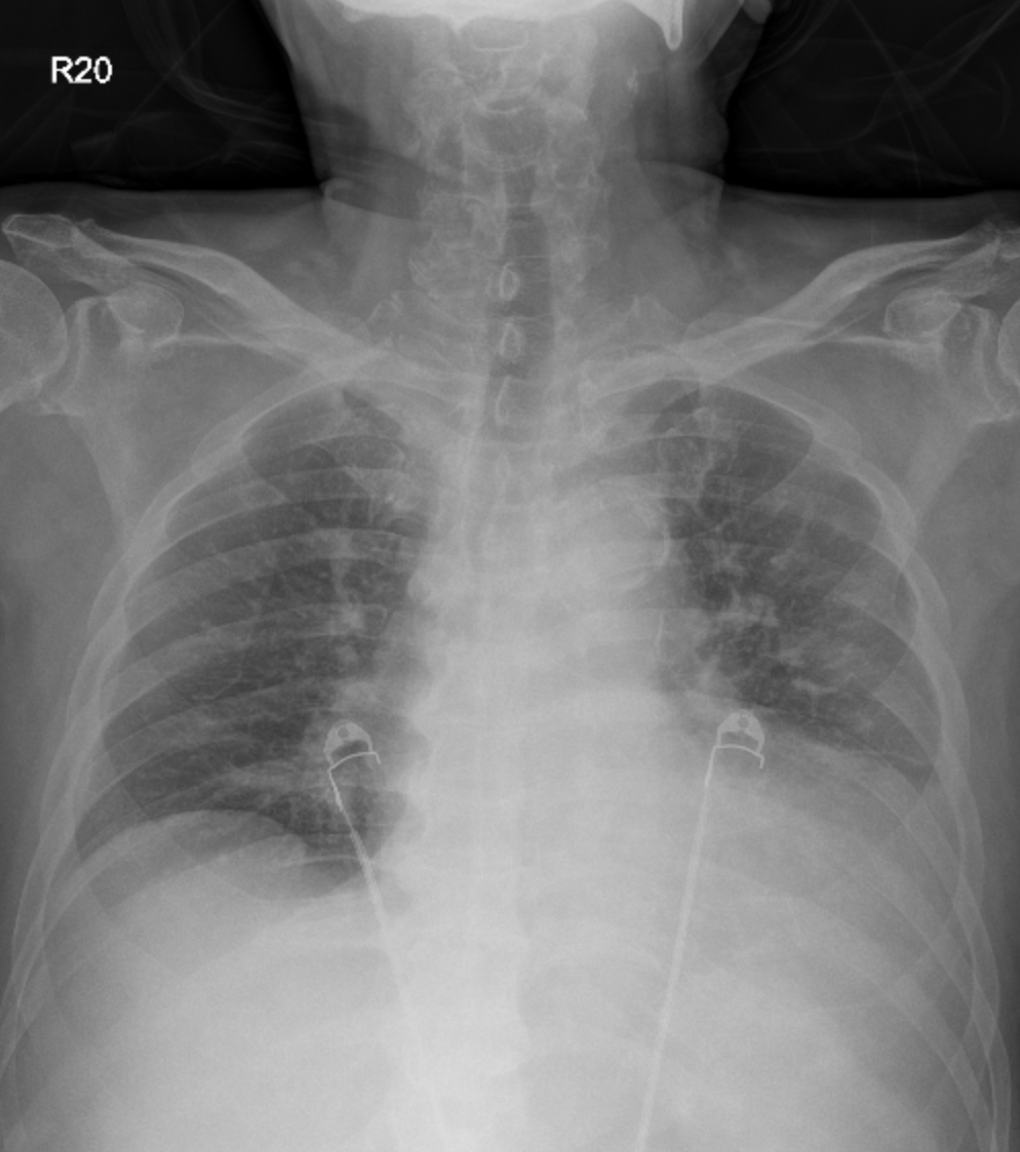

Relevant Test Results Prior to Catheterization

Electrocardiography suggested an inferior-posterior STEMI with probable left main equivalent. Echocardiography showed preserved left ventricular ejection fraction with regional wall motion abnormalities. Chest X-ray showed cardiomegaly with mild pulmonary congestion. Laboratory results revealed normal hemoglobin (16.3 g/dL), leukocytosis (26.09 ¡¿ 10©ø/¥ìL, segmented neutrophils 88.5%), elevated creatinine (2.04 mg/dL), high-sensitivity troponin T (37.66 ng/L) and lactate (2.68 mmol/L).